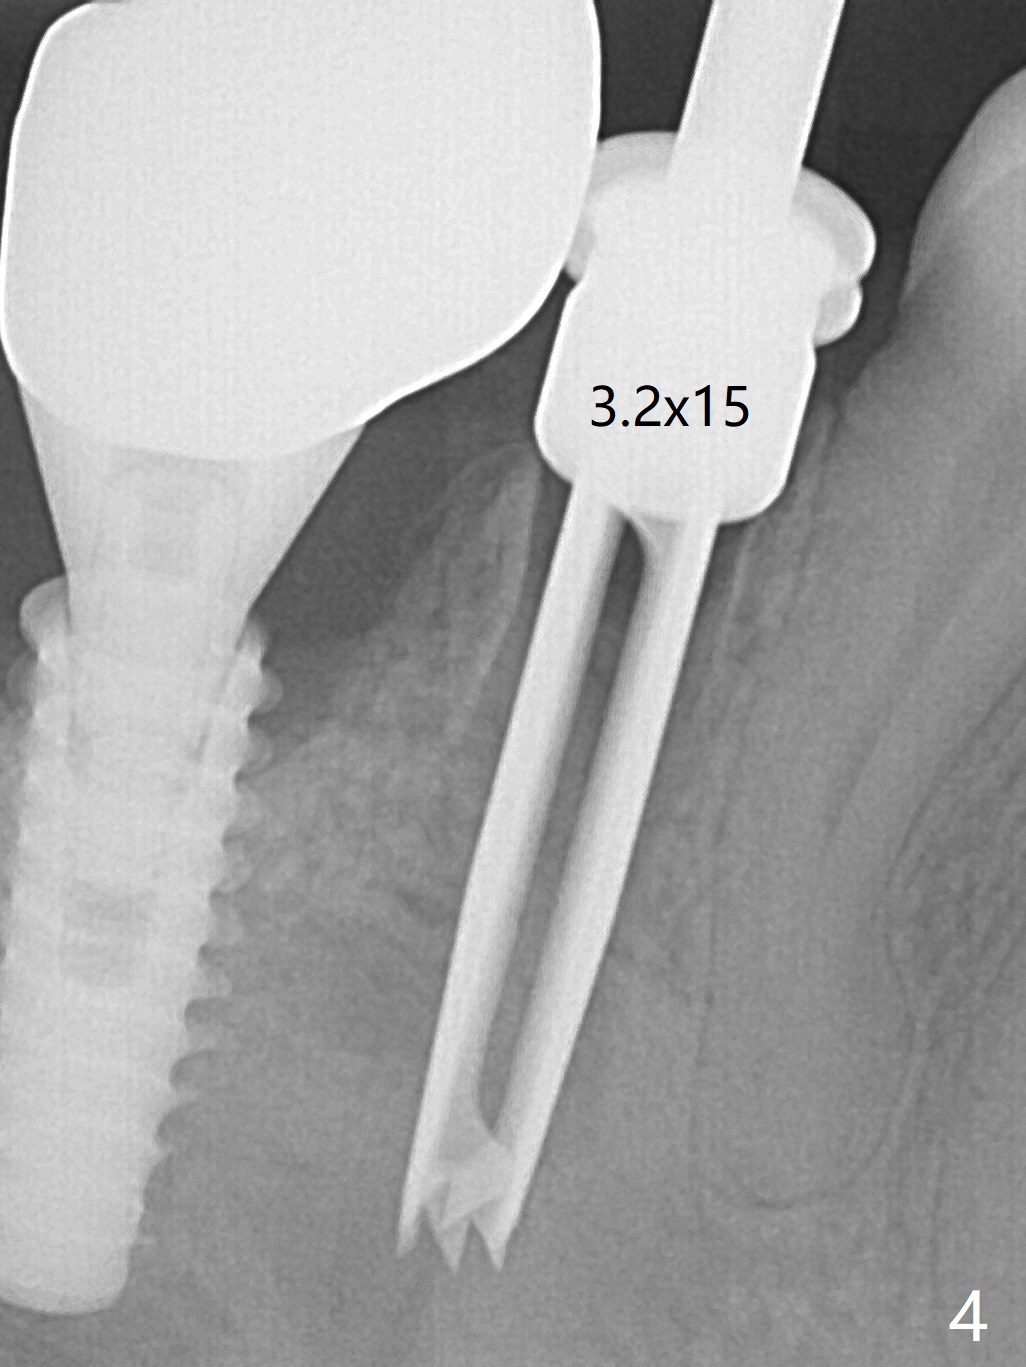

The tooth #29 has mild persistent pain radiating to the temple with mild percussion and mobility I 4.5 months post apicoectomy; the buccal recession is noticeable (Fig.1). Granulation tissue and bone graft are attached to the resected apex of the extracted tooth (Fig.2 <). The initial osteotomy with 1.5 mm drill is distal (Fig.3). After position adjustment with difficulty because of hard bone, osteotomy is finished with 2.8 and 3.2 mm Magic Drills (Fig.4). Following final drill, a 3.5x11 mm IBS implant is placed with insertion torque of 45 Ncm. With placement of a 4.5x4(4) mm abutment, Vanilla graft is placed in the buccal gap (Fig.5). Immediately postop CT shows that the implant is buccally placed (Fig.6,7 B). In fact after extraction (Fig.8), the initial osteotomy should start obliquely and as coronal and lingual as possible (Fig.9 red line). Following the initial penetration, the osteotomy should be straightened (Fig.10) so that the implant could be placed lingually (Fig11 green) to reduce buccal thread exposure. In fact there is also buccal thread exposure at #30 (Fig.12). The bone loss at #29 and 30 is minimal 4 months postop (#29, Fig.13 *)) and severe with periimplantitis at #29 one year post cementation (Fig.14). Incision will be made to exposure buccal threads of #29 and 30. If threads are within bone boundary, bone graft will be done with sticky bone after Titanium brush. If not, remove implant threads and bone graft. The worst scenario will be handled with implant removal (trephine bur 4/5 mm), either with bone graft or implant being placed lingually (IBS 3x11 mm 2-piece, to be buried, if needed (Fig.15)). Take preop photos to show #29 and 30 buccal recession and gingival erythema.